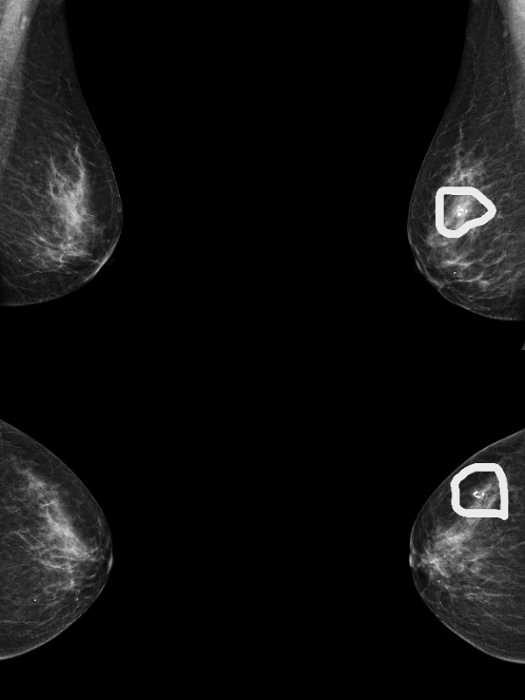

图1 患者A的钼靶图像,报告显示为正常乳腺

图3 患者B的钼靶图像,显示乳腺多发钙化灶(图中画圈处)